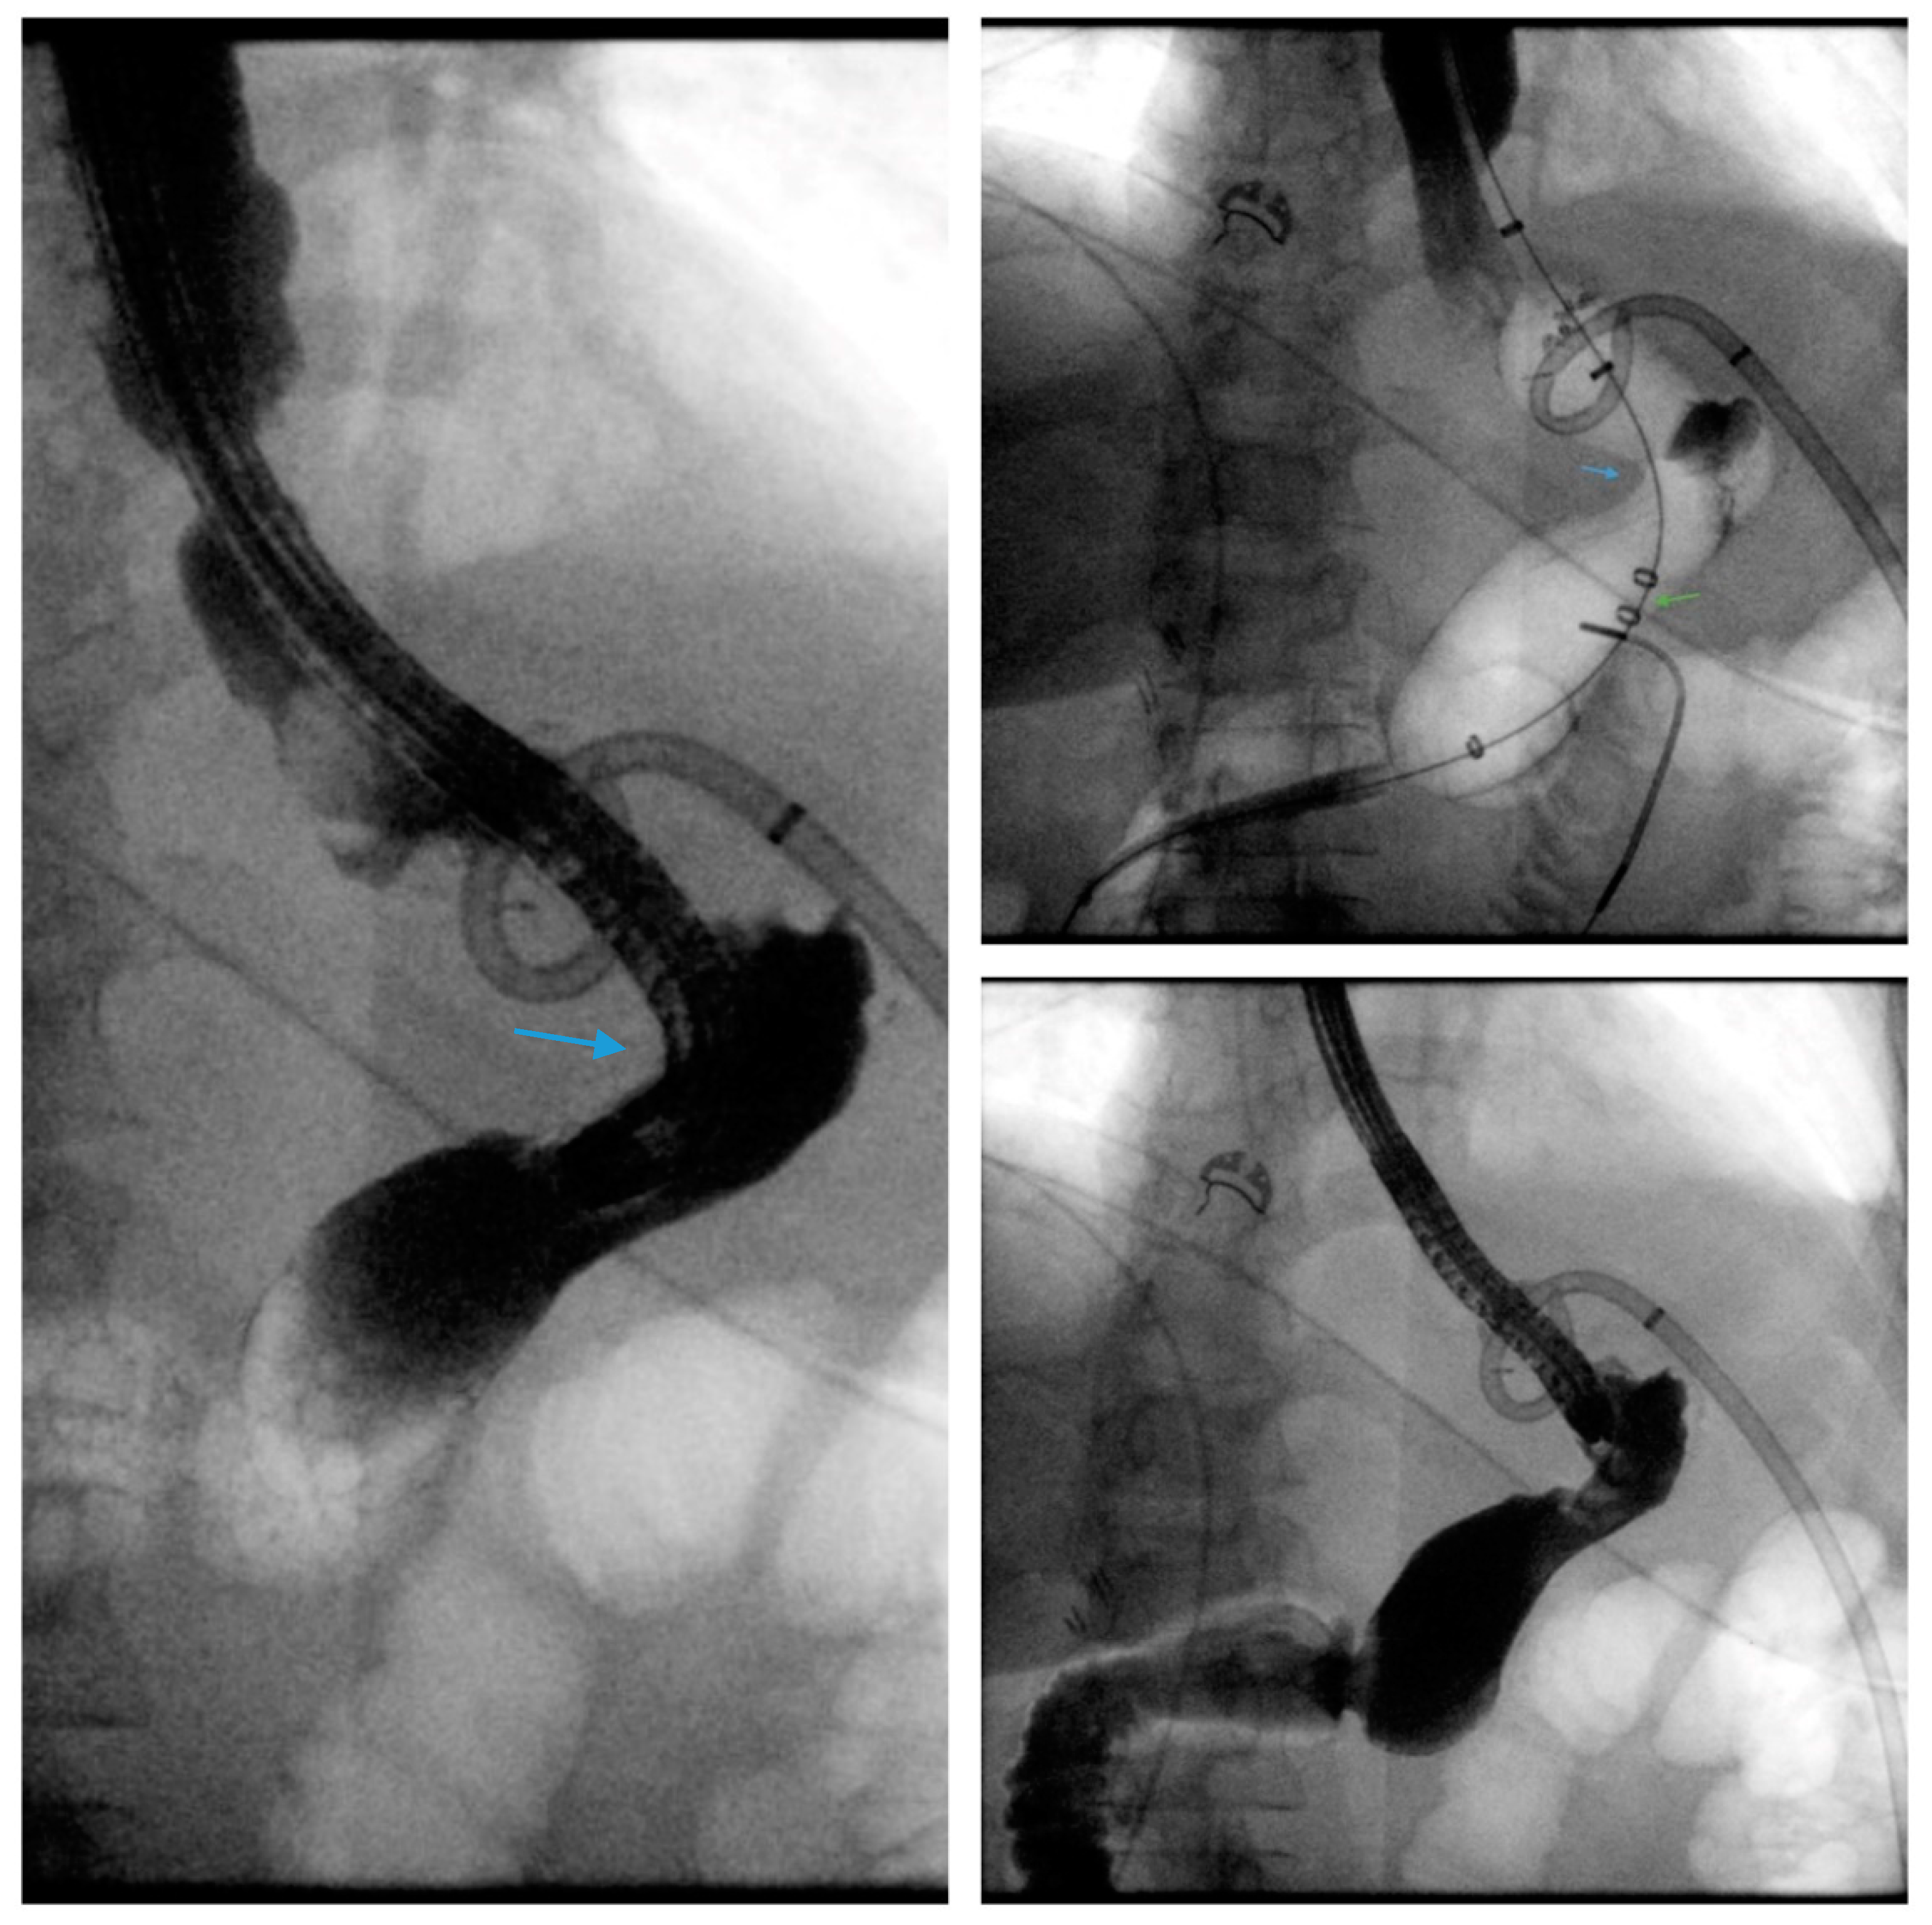

Scheme 4.

Fluoroscopic image demonstrates the placement of a 23 mm × 15 cm partially-covered esophageal self-expanding metal stent from the distal esophagus to the pylorus (arrow, top left) for the treatment of a leak in a patient following sleeve gastrectomy. Contrast injected endoscopically (arrows, top right and middle left) reveals a small, persistent sleeve leak. The endoscopic removal of the stent was subsequently attempted using a grasper (arrows, middle right and bottom left), but the stent removal was unsuccessful due to tissue ingrowth. A 23 mm × 15 cm, fully-covered, esophageal self-expanding metal stent was placed within the prior stent (arrow, bottom right) to facilitate removal after pressure necrosis of the ingrown tissue.

Scheme 5.

Axial view of a computed tomography scan of the abdomen and pelvis with contrast reveals a uniform, thin-walled, cystic lesion of the pancreas, which measures 90 mm × 52 mm × 48 mm, with peripheral calcifications with a BMI of 38 (arrow, A). Endoscopic ultrasound demonstrates an anechoic and hypoechoic lesion of the pancreatic body with two compartments, no septae or internal debris, and an associated mural nodule which was suggestive of a mucinous cystic neoplasm (arrow, B). The patient subsequently underwent a laparoscopic sleeve gastrectomy and a concurrent, open distal pancreatectomy which was complicated by a persistent pancreatic leak as well as a gastric sleeve leak (blue arrow, C) as demonstrated by contrast injected through a percutaneous drain (silver arrow, C). The percutaneous drain is redemonstrated on upper endoscopy (arrow, D). Note the additional percutaneous drain in the pancreatic bed for the postoperative leak (green arrows, C,G). Endoscopic internal drainage using transgastric double-pigtail stents was performed as demonstrated on fluoroscopic imaging (arrows, E,G) and endoscopy (arrow, F). After a prolonged course, the patient had a complete recovery, and a follow-up CT scan of the abdomen and pelvis confirmed the resolution of the leak and the removal of the double-pigtail stents and percutaneous drains (H).